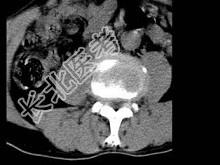

- 单项选择题男,45岁, 腰痛,结合图像, 最可能的诊断是 ( )

A、椎间盘膨出

B、椎间盘突出

C、椎间盘未见异常

D、腰椎骨质增生

E、前纵韧带钙化